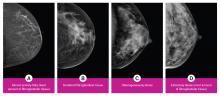

AI is also helping simplify complex tasks and help reduce the reading time on involved exams. One example of this is in 3-D breast tomosythesis with hundreds of images, which is rapidly replacing 2-D mammography, which only produces 4 images. Another example is automated image reconstruction algorithms to significantly reduce manual work. AI also is now being integrated directly into several vendors' imaging systems to speed workflow and improve image quality.

In addition to women with dense breasts, there are also other women for whom mammographic screening is not really enough, which is why research needs to continue in this field. Dr. Wendie Berg, a leading breast cancer specialist, talks with ITN about new research and advancements in breast imaging technology.

Dr. Berg, MD, PhD, FACR, FSBI, is Professor of Radiology at the University of Pittsburgh School of Medicine and Magee-Womens Hospital of UPMC, specializing in breast imaging. She is also the Chief Scientific Advisor to DenseBreast-info.org. A renowned expert, she writes and co-edits one of the leading textbooks on the topic, Diagnostic Imaging: Breast, currently in its third edition, and has co-authored over 120 peer-reviewed research publications.

AI Provides Accurate Breast Density Classification

Breast Density | April 14, 2023

It has long been said that a national reporting standard is needed in order to ensure all American women receive at least the same basic information regarding breast density, and a spotlight put on the importance of routine breast imaging. Dr. Wendie Berg, a leading breast cancer specialist, shares with ITN what is being done in the fight against breast cancer and the importance of this standardization in reporting for women.